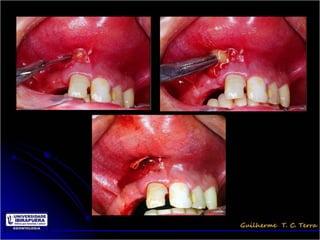

Abscesso Palatino

Abscesso vestibular

Pericoronarite

• Infecção dos tecidos moles (Opérculo)

que recobrem a coroa de um dente

incluso

Tratamento das infecções odontogênicas

• Drenagem da infecção

– Incisão abaixo do ponto de flutuação

– Colocação do dreno

– Sutura